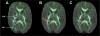

Methods: A cohort of 60 preterm newborns (24-32 wk gestational age) was assessed using early and near-term magnetic resonance imaging (MRI) studies. Red blood cell fatty acid composition was analyzed coordinated with each scan. Outcome at a mean of 33 mo corrected age was assessed using the Bayley Scales of Infant Development, 3rd edition.

Results: Adjusting for confounders, a 1% increase in postnatal docosahexaenoic acid (DHA) levels at early MRI was associated with 4.3-fold decreased odds of intraventricular hemorrhage, but was not associated with white matter injury or cerebellar haemorrhage. Higher DHA and lower linoleic acid (LA) levels at early MRI were associated with lower diffusivity in white matter tracts and corresponding improved developmental scores in follow-up.